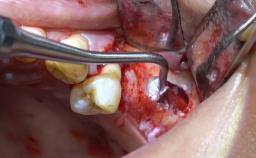

- Details of surgical techniques for SFE